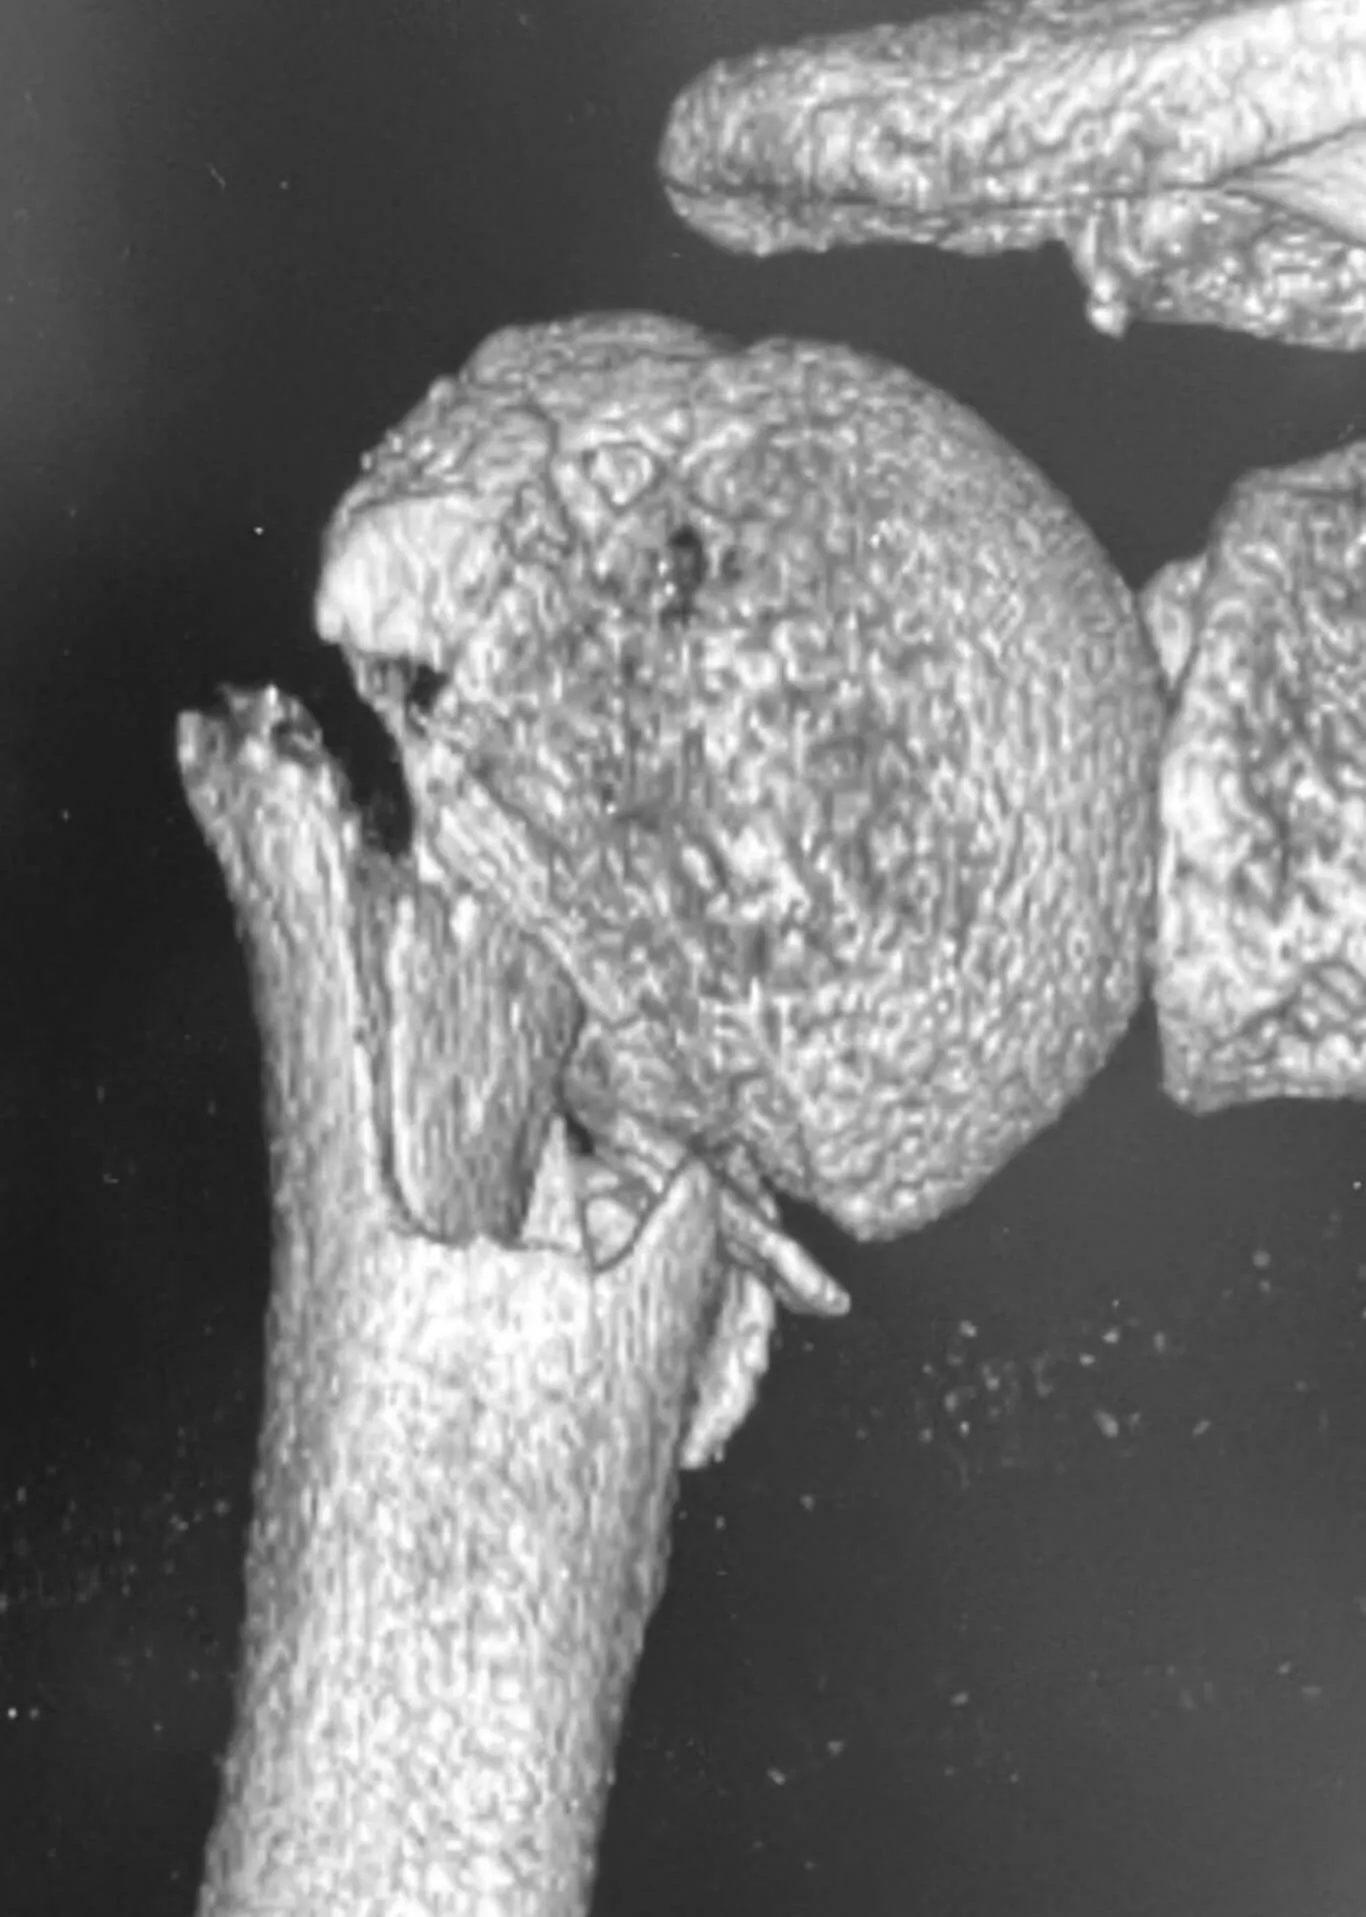

Przed operacją

Złamanie bliższego końca kości ramiennej

Pacjentka, lat 76, doznała złamania w wyniku upadku z wysokości własnej. Złamanie miało charakter wieloodłamowy ze znacznym przemieszczeniem kątowym odłamów. Bez leczenia operacyjnego chora nie odzyskałaby dobrego zakresu ruchomości i siły mięśniowej.